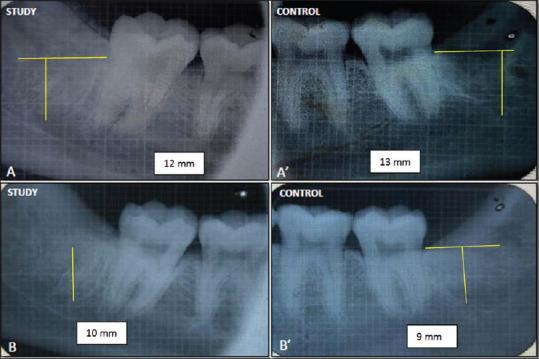

This split-mouth prospective trial constituted prophylactic removal of M3Ms with Sticky bone grafted in the study site as a primary predictor variable. Patients underwent 3 months of mandatory follow-up where pain, swelling, interincisal mouth opening, and gingival healing were measured on the 3, 7, and 14 day using the Numeric Rating Scale, anatomic landmarks, steel metric ruler, and criteria given by Landry . respectively. Radiological healing was calculated based on the height of the socket, Kelly's Index, and histogram values immediately after the procedure at 1 week, 1 month, and 3 months, respectively. Statistical comparison was made using Paired -test. < 0.05 was considered significant.

本双盲前瞻性试验将在研究部位植入粘性骨预防性拔除M3M作为主要预测变量。患者接受3个月的强制随访,分别在第3、7和14天使用数字评分量表、解剖标志、钢尺以及兰德里给出的标准测量疼痛、肿胀、切牙间开口度和牙龈愈合情况。分别在术后即刻、1周、1个月和3个月根据拔牙窝高度、凯利指数和直方图值计算放射学愈合情况。采用配对t检验进行统计学比较。P<0.05被认为具有显著性。